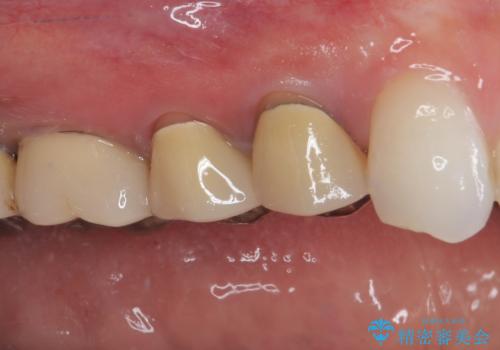

まずは根管治療を行い、痛みの消退を確認してからオールセラミッククラウンによる補綴治療を行うこととしました。

黄ばんできてしまった小臼歯部のクラウンは、根尖部に症状を認めないため、そのままオールセラミッククラウンによる補綴治療を行うこととしました。

初回の根管治療で痛みや違和感は消退したため、その後は速やかに補綴治療を行いました。